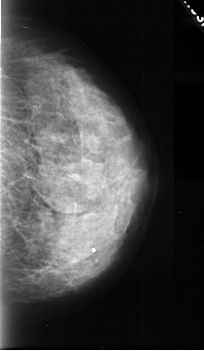

A_1043_1.LEFT_CC

LEFT_CC LINES 4426 PIXELS_PER_LINE 2536 BITS_PER_PIXEL 16 RESOLUTION 42 OVERLAY